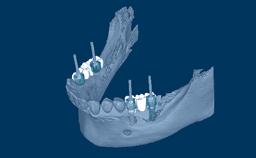

种植体支持式固定义齿旨在为缺失牙齿提供修复义齿,从而能承担相应的功能性需求,并且准确模拟缺失牙单位的美学效果。理想情况下,修复体应与周围牙齿难以分辨。为此,临床医生必须选择最佳的可用材料,来应对临床病情的种种挑战。本模块将讨论可用于制作种植体支持式固定义齿的牙科材料,以及为每个病例选择最合适的材料的基本原则。